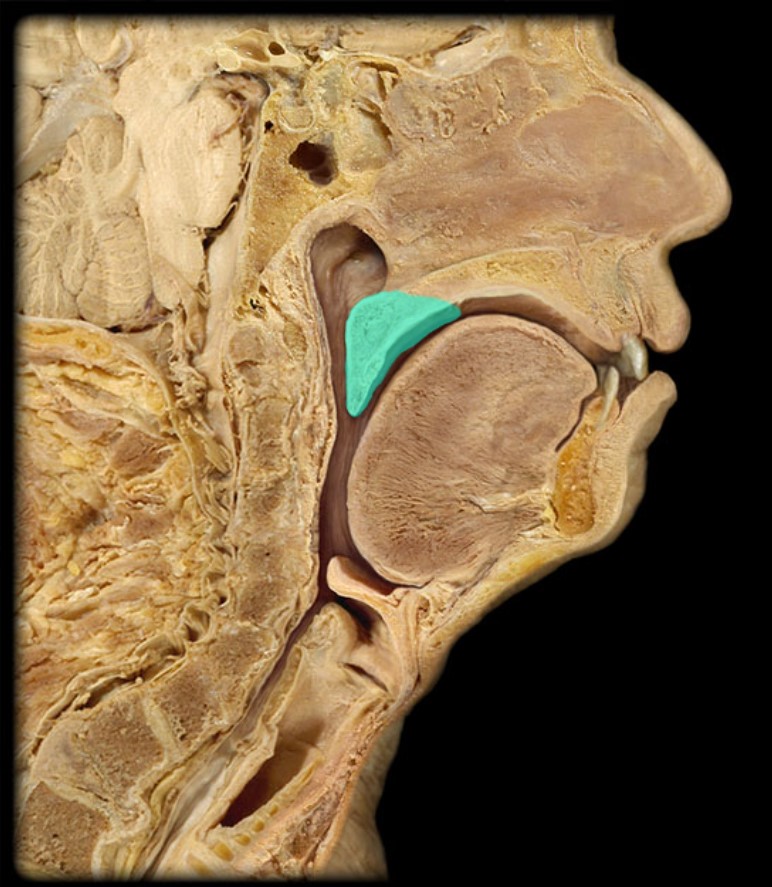

Anatomy 5 - Bifurcated Skull

29 Terms

Pharyngeal Tonsil

21

New cards

Auditory Hiatus

22

New cards

Torus Tubarius

23

New cards

Sphenoid Sinus

24

New cards

Inferior Nasal Concha

25

New cards

Middle Nasal Concha

26

New cards

Superior Nasal Concha

27

New cards

Nasal Vestibule

28

New cards

External Nares

29

New cards

Frontal Sinus